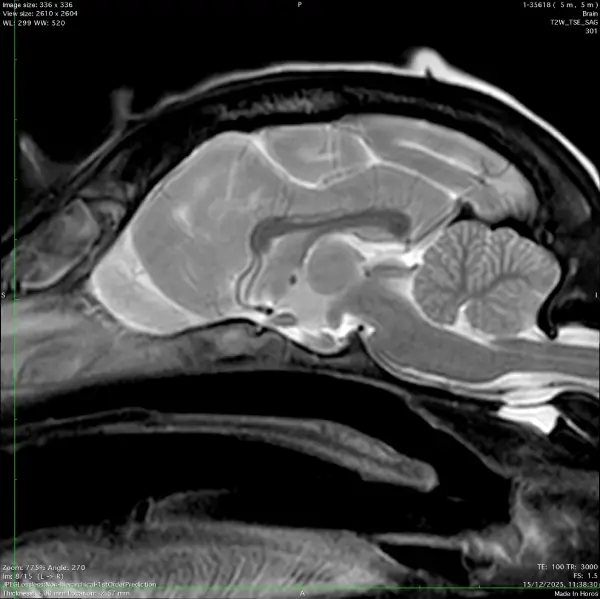

- MRI & CT Scans

- MRI scans: MRI gives excellent detail of the brain, spinal cord and associated nerves. All patients having an MRI scan will need a general anaesthetic.